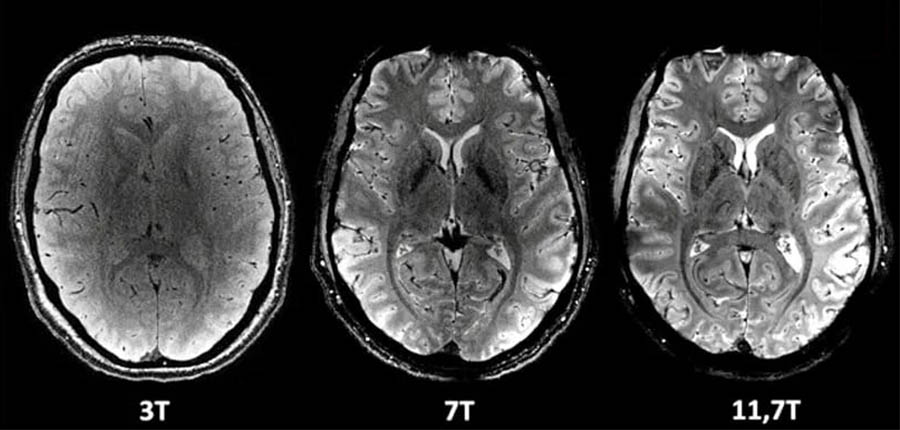

Les images sont les plus précises jamais publiées. Avec 11,7 teslas, l'IRM Iseult a une puissance bien supérieure aux outils de l'imagerie médicale jusqu'à maintenant utilisés dans les centres hospitaliers et les centres de radiologie (de 1,5 à 3 teslas) ou à d'autres appareils (à 7 teslas).